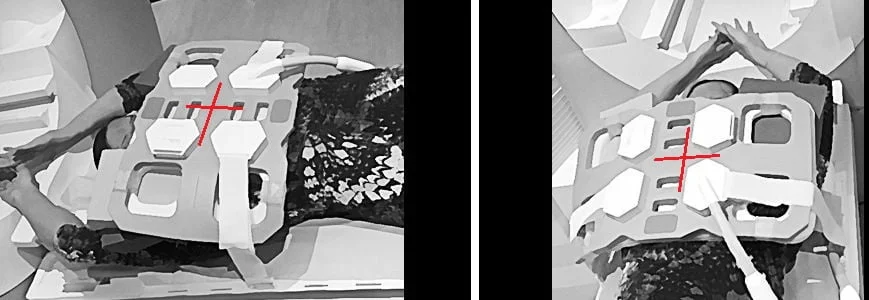

Positioning for arm down MRA and MRV of subclavians

MRA (magnetic resonance angiography) and MRV (venography) of subclavian and neck artery positioning photo

Positioning for arm up MRA and MRV of subclavians

MRA subclavian positioning arm up - MRI